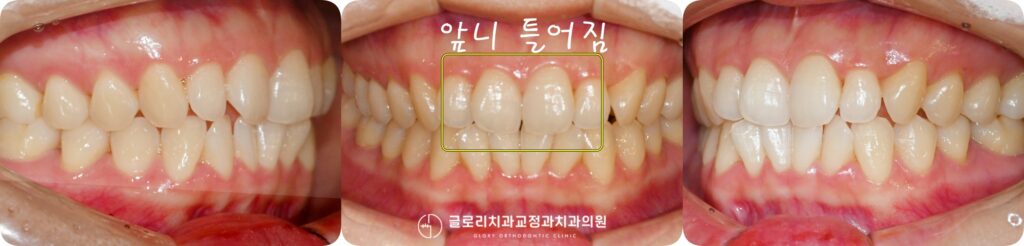

중화동 치과 에서 준비한 정면 사진을 보면 현재 전치부에 총생이 있고 상악 앞니가 안쪽으로

틀어진 형태를 보이고 있습니다. 그로인해 앞니가 고르지 않게 보이고

치아 사이 청결관리도 어려울 것으로 예측됩니다.

이번 중화동 치과 에서 준비한 예시 케이스의 경우

치열의 틀어짐 정도가 크지 않고 교합에도 큰 문제가 없는 것으로

판단되어 상악만 선택적으로 교정을 진행할 수 있습니다.

중화동 치과 와 부분교정이 마무리된 구강을 살펴보겠습니다.

초진 시 안쪽으로 돌아가 있던 전치부가 가지런하게 자리를 잡았고 인접치와도

자연스러운 조화를 이룹니다.

측면에서 살펴보면 더욱 확실히 알 수 있는데 치아의 전후 위치가 고르게

맞춰지면서 전체 흐름이 한결 안정하게 정돈된 모습입니다.

이번 케이스의 경우 상악만 부분적으로 진행했기 때문에 하악 치열에는 별다른 변화가

없습니다. 다만 하전치에도 총생이 일부 관찰되는 만큼, 상악 교정이 안정하게 유지되는

것을 확인한 이후 추후 아래 역시 치료를 함께 고려해볼 수 있습니다.